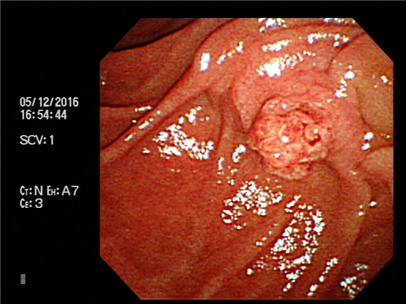

증례 4. 황달 증상으로 내원한 환자에서 담도내시경을 통해 진단된 십이지장 유두부 종양 2예